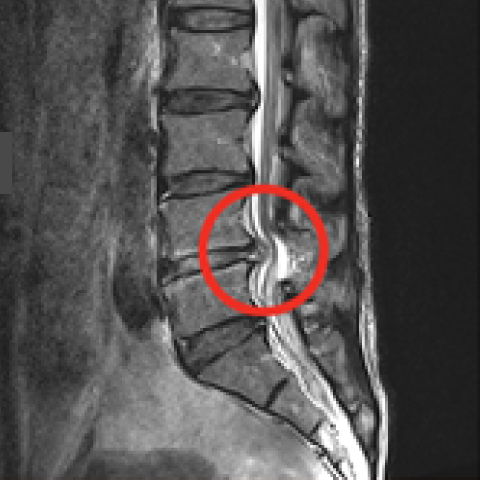

터진 디스크를 내시경으로 제거하는 모습